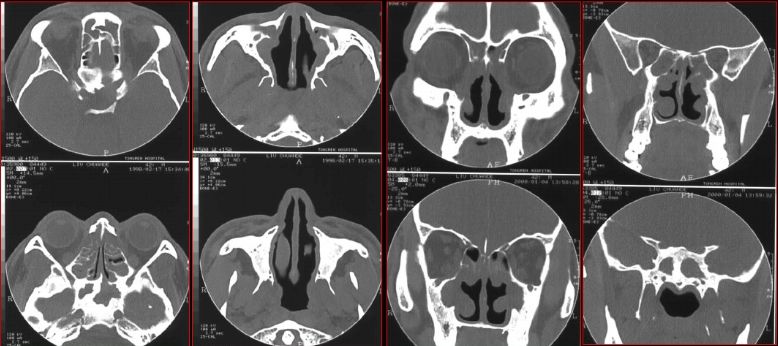

鼻窦炎—骨质改变

鼻窦炎—骨质增生

鼻窦炎—骨质增生及脑膜炎